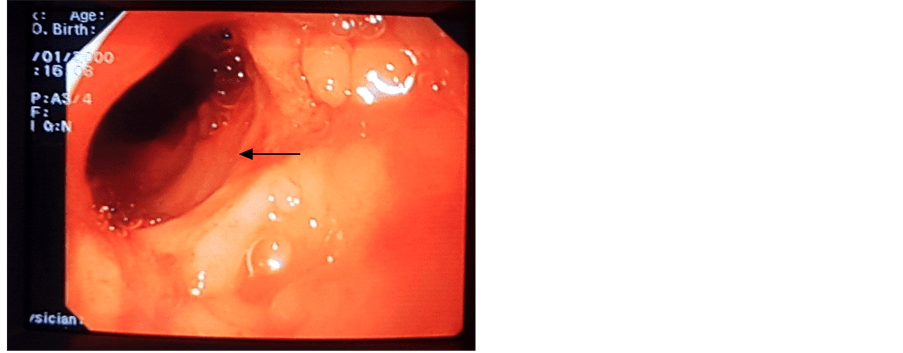

Pediatric Ulcerative Colitis Ulcerative Colitis Is A Chronic Inflammatory Bowel Disease (Ibd) In Which The Lining Of The Large Intestine (Colon Or Bowel) And Rectum Becomes Inflamed.

Uc Causes Tiny Sores In The Large Intestine Lining, Which Bleed And Produce Mucus And Pus.

Ulcerative colitis in children 10 years old or younger the onset and course of ulcerative colitis diagnosed in 38 children at or before 10 years of age were reviewed. Ulcerative colitis is a chronic (reoccurring) condition. However, experts believe that it may start when bacteria or a virus triggers an inflammatory reaction in the colon.